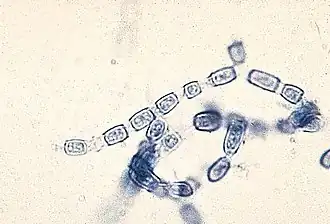

Anders dan bij de blastische vormen worden bij thallisch arthrische conidiogenese voor de sporenvorming eerst de septa gevormd. Daartoe moet een schimmeldraad eerst volgroeid zijn, waarna deze op onregelmatige afstanden dubbele tussenwanden vormt. De individuele cellen die zo ontstaan scheiden zich op een schizolytisch genoemde wijze van elkaar af en beginnen zich te differentiëren, zodat een keten van korte cilindervormige sporen ontstaat, de zogeheten artroconidiën, die gelijktijdig met elkaar verbonden lijken te zijn. Bij een variant van deze conidiogenese vormen zich afwisselend cellen en sporen, de tussenliggende cellen degenereren, sterven af en maken zo de tussenliggende arthroconidiën door rexolitische dehiscentie vrij.

.jpg) Macroconidia van de schimmel Epidermophyton floccosum de veroorzaker van Tinea cruris

Macroconidia van de schimmel Epidermophyton floccosum de veroorzaker van Tinea cruris -

Macroconidia van de schimmel Microsporum canis